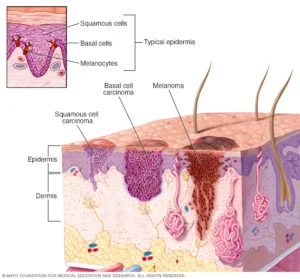

سرطان الخلايا الحرشفية (Squamous Cell Carcinoma) هو ثاني أكثر أنواع سرطان الجلد شيوعًا، فما هي أعراضه وأسبابه؟ وما طرق علاجه المحتملة؟ لنتعرف على ذلك في

سرطان الخلايا القاعدية الوحمانية عبارة عن نوع من سرطان الجلد. يبدأ سرطان الخلايا القاعدية الوحمانية في الخلايا القاعدية — نوع من الخلايا الموجودة داخل الجلد

الورم الميلانيني نوعٌ من سرطان الجلد ينشأ في الخلايا الميلانينية. والخلايا الميلانينية مسؤولة عن إنتاج الصبغة التي تمنح الجلد لونه. ويُطلق على الصبغة الميلانين. ينشأ

عادة ما يظهر سرطان الجلد – نمو غير الطبيعي في خلايا الجلد – على الجلد المعرَّض للشمس. ولكن قد يظهر هذا النوع الشائع من السرطان